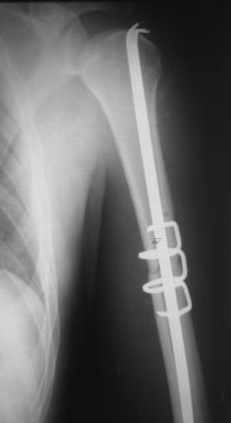

Re: Перелом плеча

Приложение как пример.

Что иллюстрирует этот пример? Это была множественная травма? Если это был изолированный перелом, то "золотой стандарт" - консервативное лечение.

Консервативно он уже лечился до этой операции в течение трёх с половиной месяцев.

А именно такой вариант операции выбран из экономических соображений.

вообще, торчашие в субакромиальное пространство шипы оставляют неизгладимое впечатление. Не думаю, что таким имплантом есть смысл гордиться